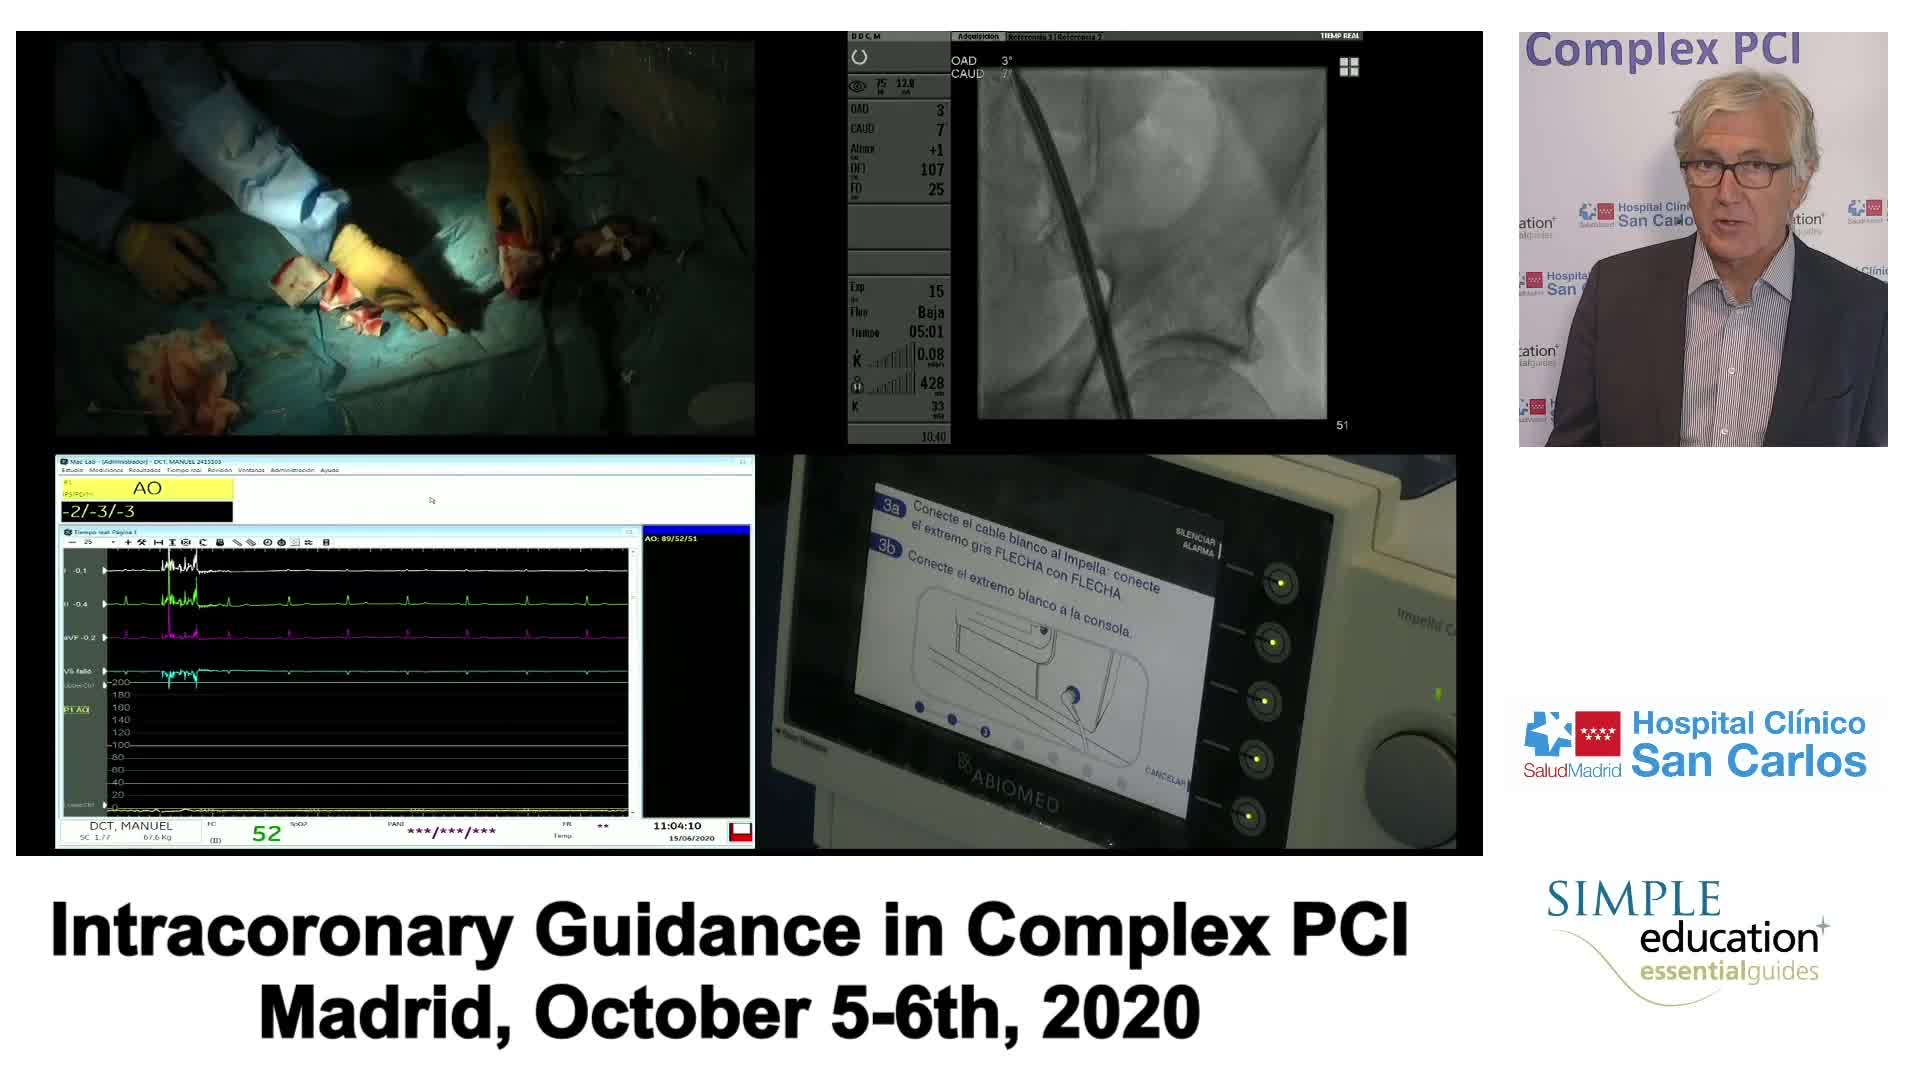

Complex PCI eCourse Madrid Day Two